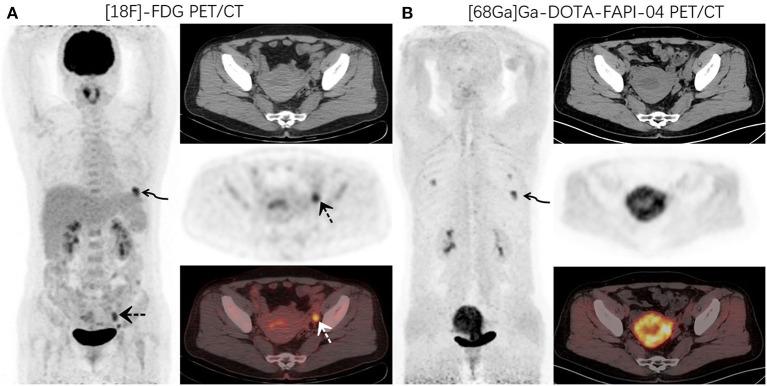

This study aimed to investigate the physiological distribution characteristics of Ga-DOTA-FAPI-04 in the ovary, and assess the feasibility of early diagnosis of primary ovarian disease with Ga-DOTA-FAPI-04 PET/CT. We retrospectively analyzed the data of patients who received F-FDG and Ga-DOTA-FAPI-04 PET/CT scanning in the Nuclear Medicine Department of our hospital within 3 days from September 2020 to January 2021. We selected the data in which ovaries showed abnormal FDG activity. Patients with abnormal ovarian FDG uptake with focus confirmed by pathological biopsy or clinical follow-up as pathological changes were excluded. The uptake of tracers (F-FDG and Ga-FAPI) was semi-quantitatively analyzed. This study included 14 patients (average age was 38.6). Physiological ovarian uptake was mostly unilateral, and there was no significant difference in SUVmax between the left and right sides (FDGt = 0.272, FAPIt = 0.592). The ovary SUVmax of FDG (4.89 ± 1.84) was statistically significantly higher than that of FAPI (1.53 ± 0.37). The Le/Li ratio on FDG is 3.38 ± 1.81, TBR is 5.81 ± 1.98, while the Le/Li ratio on FAPI is 3.57 ± 1.26, TBR is 0.94 ± 0.19. Our research shows that ovarian functional or pathological changes can be manifested as FDG avid, while Ga-DOTA-FAPI-04 has no physiological accumulation in the ovary and is not affected by the menstrual cycle. Therefore, Ga-DOTA-FAPI-04 has unique advantages in the diagnosis of ovarian diseases, and can identify them early and accurately.

本研究旨在探讨Ga-DOTA-FAPI-04在卵巢中的生理分布特征,并评估Ga-DOTA-FAPI-04 PET/CT早期诊断原发性卵巢疾病的可行性。我们回顾性分析了2020年9月至2021年1月期间在我院核医学科3天内接受F-FDG和Ga-DOTA-FAPI-04 PET/CT扫描的患者数据。我们选择了卵巢显示FDG活性异常的数据。经病理活检或临床随访证实有病变的卵巢FDG摄取异常患者被排除。对示踪剂(F-FDG和Ga-FAPI)的摄取进行半定量分析。本研究纳入14例患者(平均年龄38.6岁)。生理性卵巢摄取大多为单侧,左右两侧SUVmax无显著差异(FDG:t = 0.272,FAPI:t = 0.592)。FDG的卵巢SUVmax(4.89±1.84)在统计学上显著高于FAPI(1.53±0.37)。FDG的Le/Li比值为3.38±1.81,TBR为5.81±1.98,而FAPI的Le/Li比值为3.57±1.26,TBR为0.94±0.19。我们的研究表明,卵巢功能或病理变化可表现为FDG摄取增加,而Ga-DOTA-FAPI-04在卵巢中无生理性积聚,且不受月经周期影响。因此,Ga-DOTA-FAPI-04在卵巢疾病诊断中具有独特优势,能够早期准确识别这些疾病。